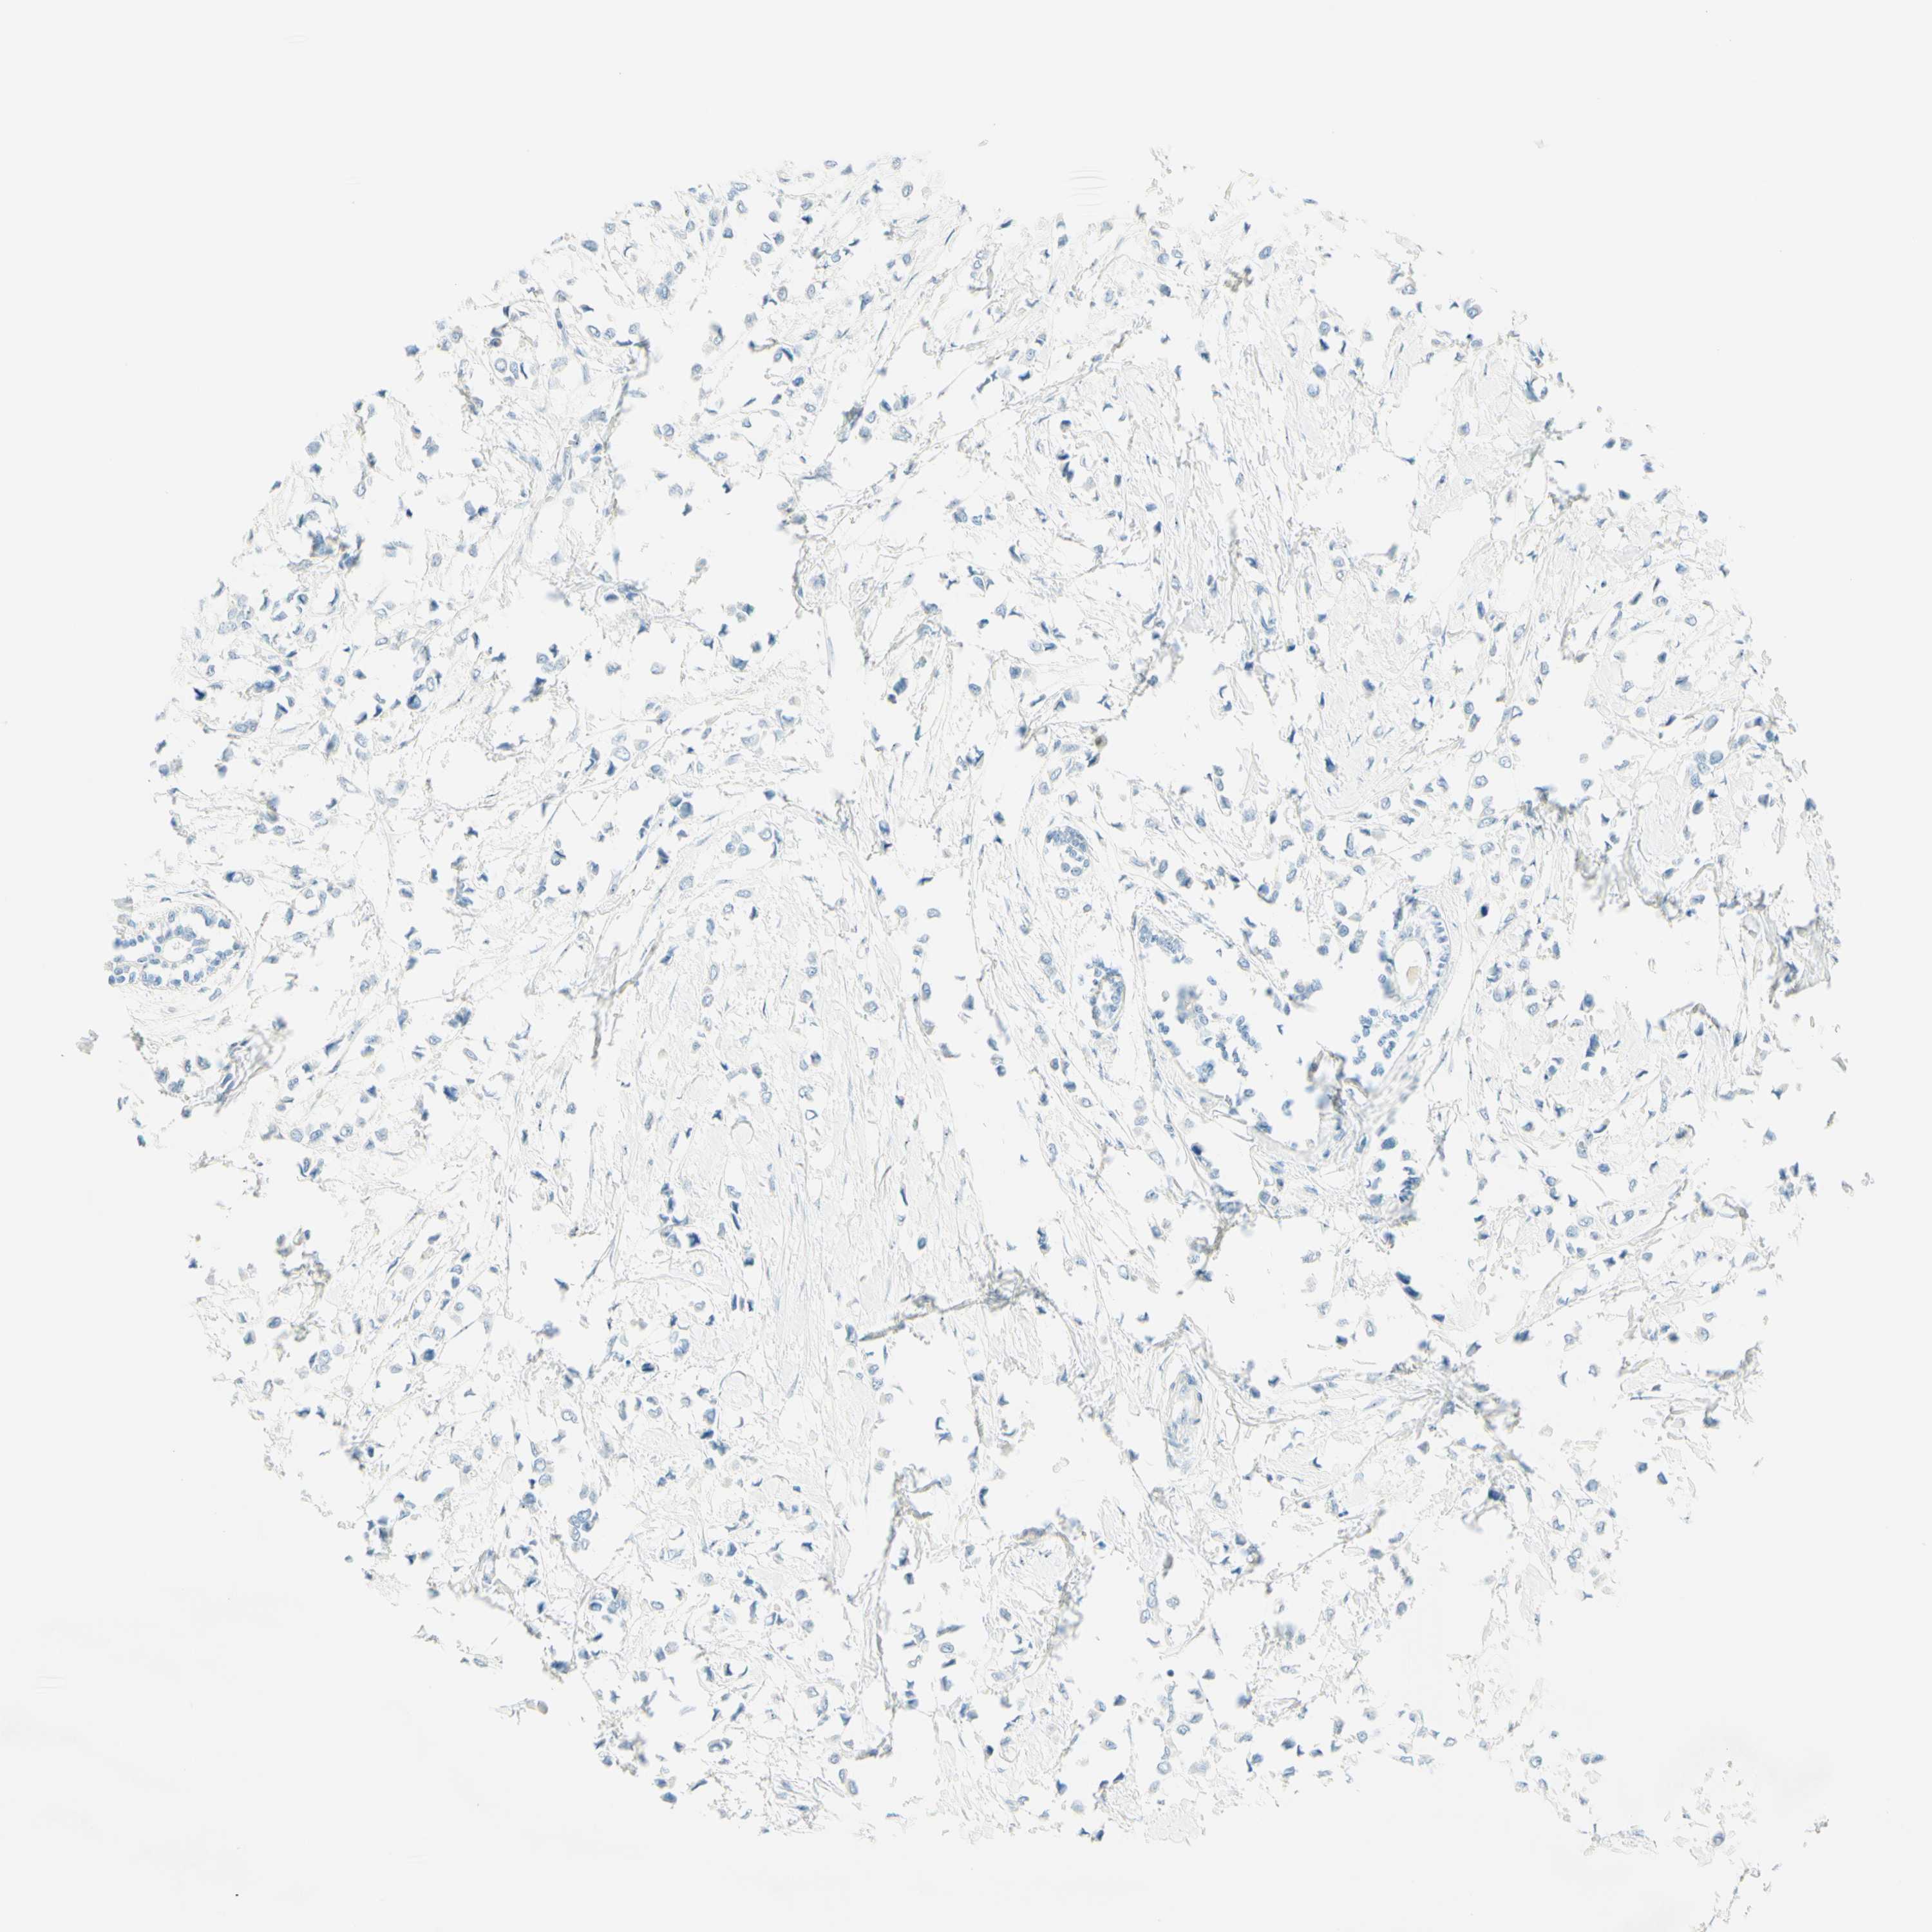

CANCER BREAST CANCER Show tissue menu

BRCA TCGA BRCA VALIDATION PROTEIN EXPRESSION